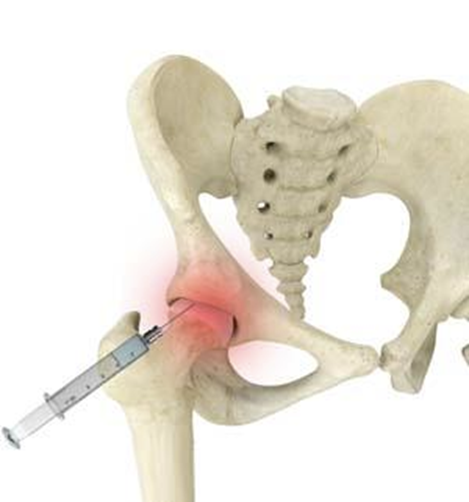

- Injections: Corticosteroids for inflammation or hyaluronic acid to lubricate the joint.

When conservative methods fall short, regenerative medicine offers innovative solutions:

1. Platelet-Rich Plasma (PRP) Therapy

- How It Works: Concentrated platelets from the patient’s blood are injected into the hip to release growth factors that reduce inflammation and stimulate tissue repair.

- Benefits: Minimally invasive, quick recovery, and potential to delay surgery.

2. Stem Cell Therapy

- How It Works: Mesenchymal stem cells (harvested from Wharton Jelly/Placenta Cord Blood) are injected to promote cartilage regeneration and modulate inflammation.

- Benefits: May restore joint function and reduce pain; often combined with PRP for enhanced effects.

Note: While regenerative therapies show promise, they are not cures. Research is ongoing, and outcomes vary based on disease severity and patient health. These treatments are typically explored when other options fail or as part of a holistic plan.